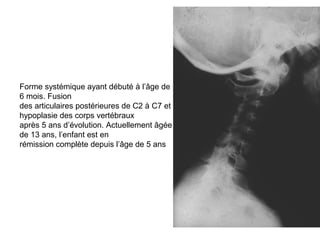

Forme systémique ayant débuté à l’âge de

6 mois. Fusion

des articulaires postérieures de C2 à C7 et

hypoplasie des corps vertébraux

après 5 ans d’évolution. Actuellement âgée

de 13 ans, l’enfant est en

rémission complète depuis l’âge de 5 ans